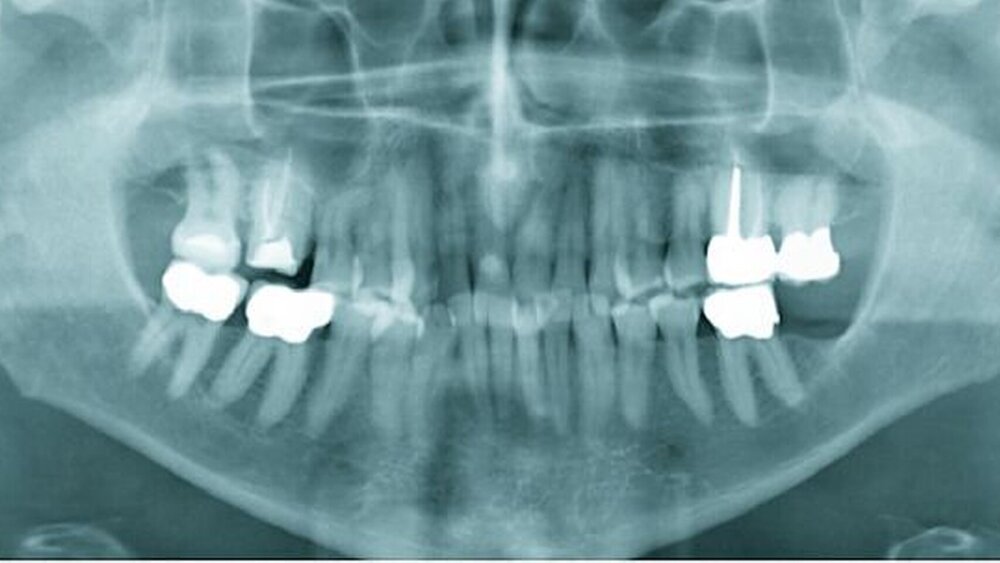

Röntgenologisch war eine geringgradige parodontale Destruktion mit generalisiert horizontalem Knochenabbau im Bereich des Oberkiefers sichtbar (Abbildung 1b). Die Auswertung des Fernröntgenseitenbildes zeigte eine neutrale Bisslage.